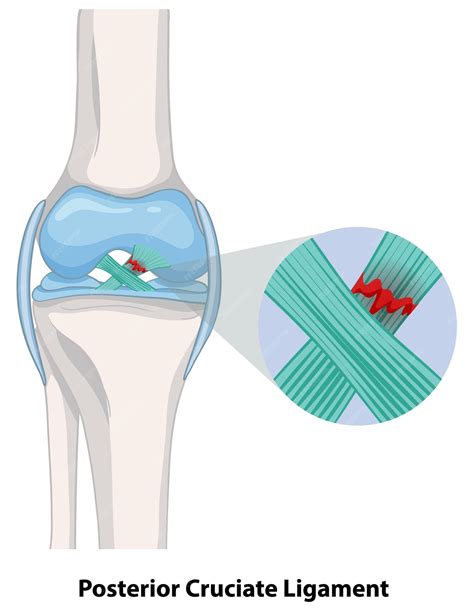

Knee joint anatomy highlighting the PCL

The PCL is situated in the back of the knee, connecting the femur (thighbone) to the tibia (shinbone). A Post Cruciate Ligament Tear typically occurs due to a direct blow to the front of the knee while it is bent, often referred to as a "dashboard injury" because it frequently happens during car accidents. Other common mechanisms include falling onto a bent knee in sports or experiencing extreme hyperextension. Recognizing the severity is the first step toward treatment: